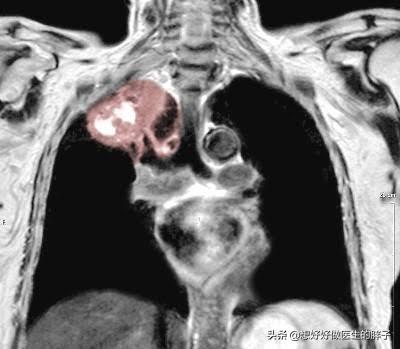

以上、心筋梗塞や狭心症による左肩の痛みを除外した病気の診断と治療について簡単にご紹介しました。もし、まだ他に疑問があるようでしたら、下記にメッセージを残していただければ、一緒に検討することができます。しかし、左肩痛の原因として、珍しいケースも考えなければなりません。例えば、左側の肺がんの可能性がありますが、これは比較的まれながんで最もよく見られるもので、私たちは次のように呼んでいます。肺溝上部のがん(肺がんの5%)。腫瘍が肺の表面を突き破って胸壁を刺激すると、肩の痛みや背中の痛みにつながり、肺上皮がん患者の16%近くが肩の痛みを最初の症状としているというデータもある。

肺疾患

肺の先端にがんや結核、胸膜癒着が起こると、まず痛み自体が肩に放散することがあり、次に腫瘍が腕神経叢神経を圧迫する傾向があるため、肩の痛みを引き起こす。激しい痛みは肩関節の運動障害を引き起こすことがある。